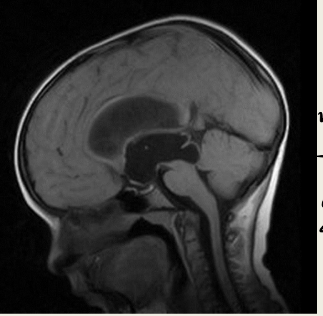

11

Q

What is this?

A

Aqueductal Stenosis